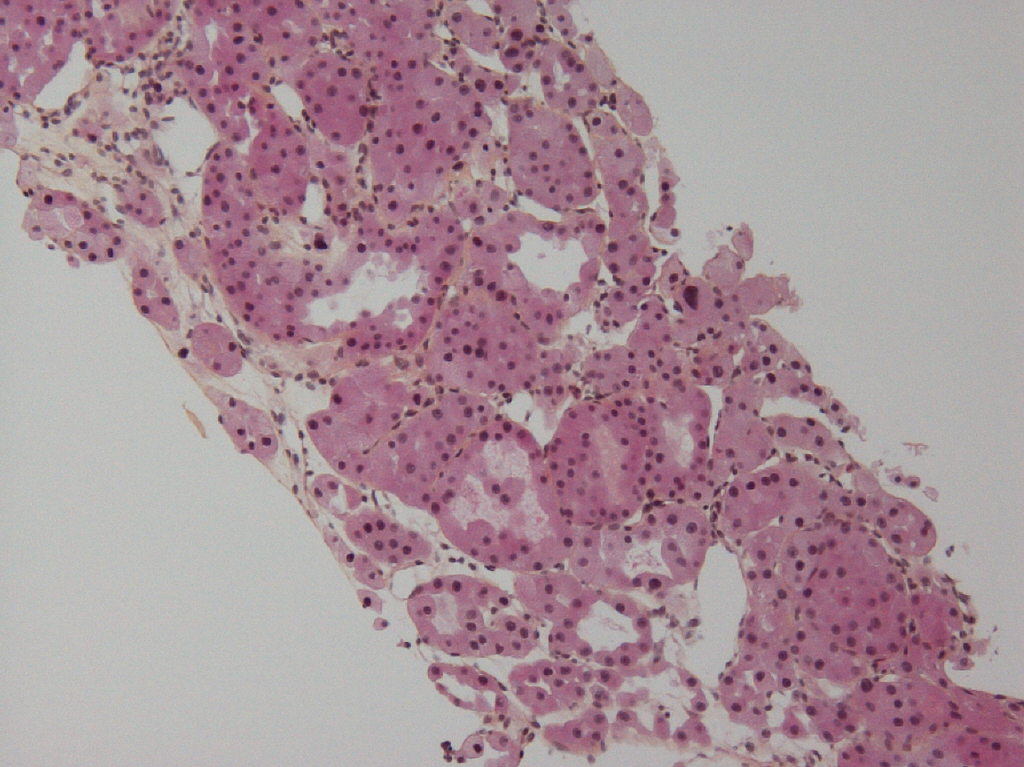

Case ID: 615

Consensus grade: I would not grade this tumor

Case description (by case creator):

oncocytoma biopsy